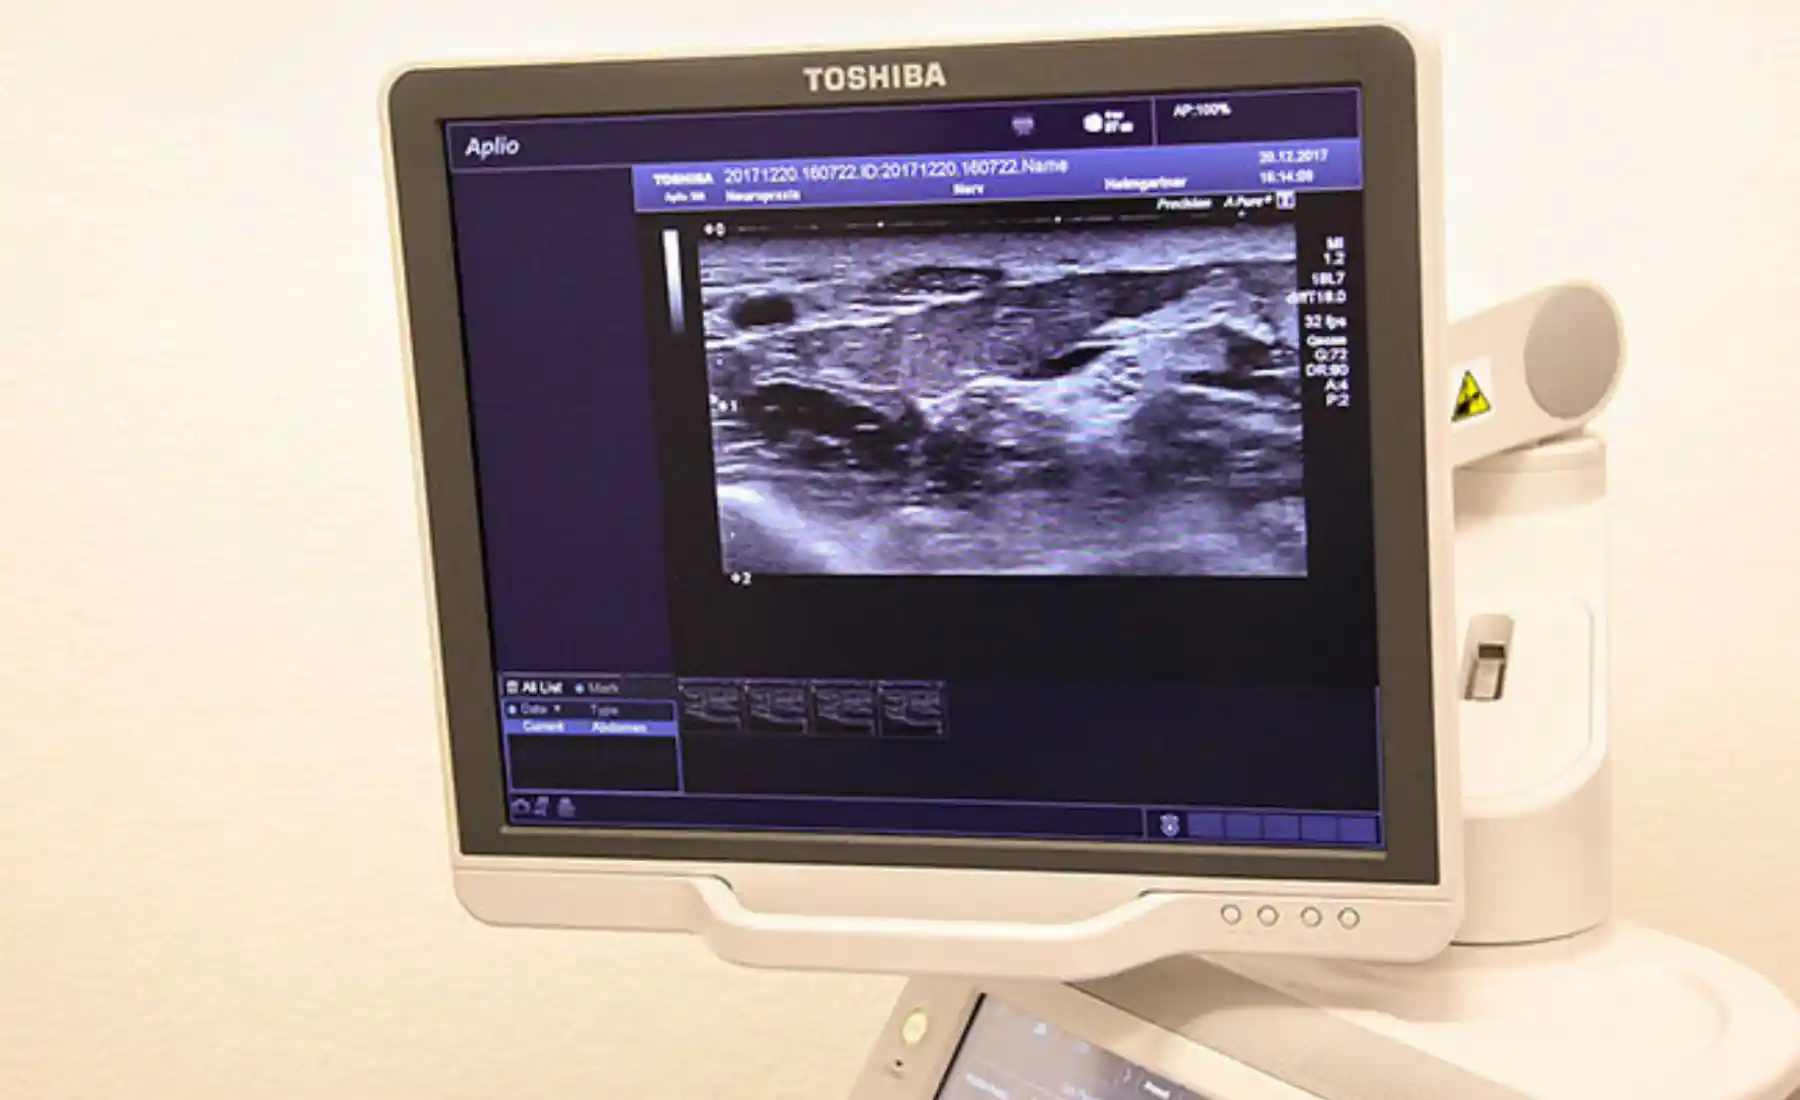

Sonographie der Nerven (MSK)

Muskuloskelettale Sonographie

Die muskuloskelettale Sonographie ermöglicht als bildgebendes Verfahren eine zuverlässige, zusätzliche Diagnostik. Neuromobil zeichnet sich durch fundierte Kenntnisse dieses Verfahrens aufgrund langjähriger Erfahrung aus.

Mit einem hochauflösenden 12 bis 24 MHz-Schallkopf kann Neuromobil Muskeln, Sehnen und Nerven optimal untersuchen. Insbesondere bei peripheren Engpasssyndromen leistet der Ultraschall als bildgebende Diagnostik gute Dienste. Sie erleichtert die neurophysiologische (Neurographie) und klinische Anamnese – wie beispielsweise die Diagnose von Karpaltunnelsyndromen.

Als engagierte Spezialisten sind wir von Neuromobil bemüht, unsere Kenntnisse wie auch die Möglichkeiten der Anwendung eines Verfahrens stets zu erweitern. Die Methode der sonographischen Nervendarstellung wird von Samuel Heimgartner beispielsweise auch bei Verdacht einer Luxation des Nervus ulnaris angewendet.